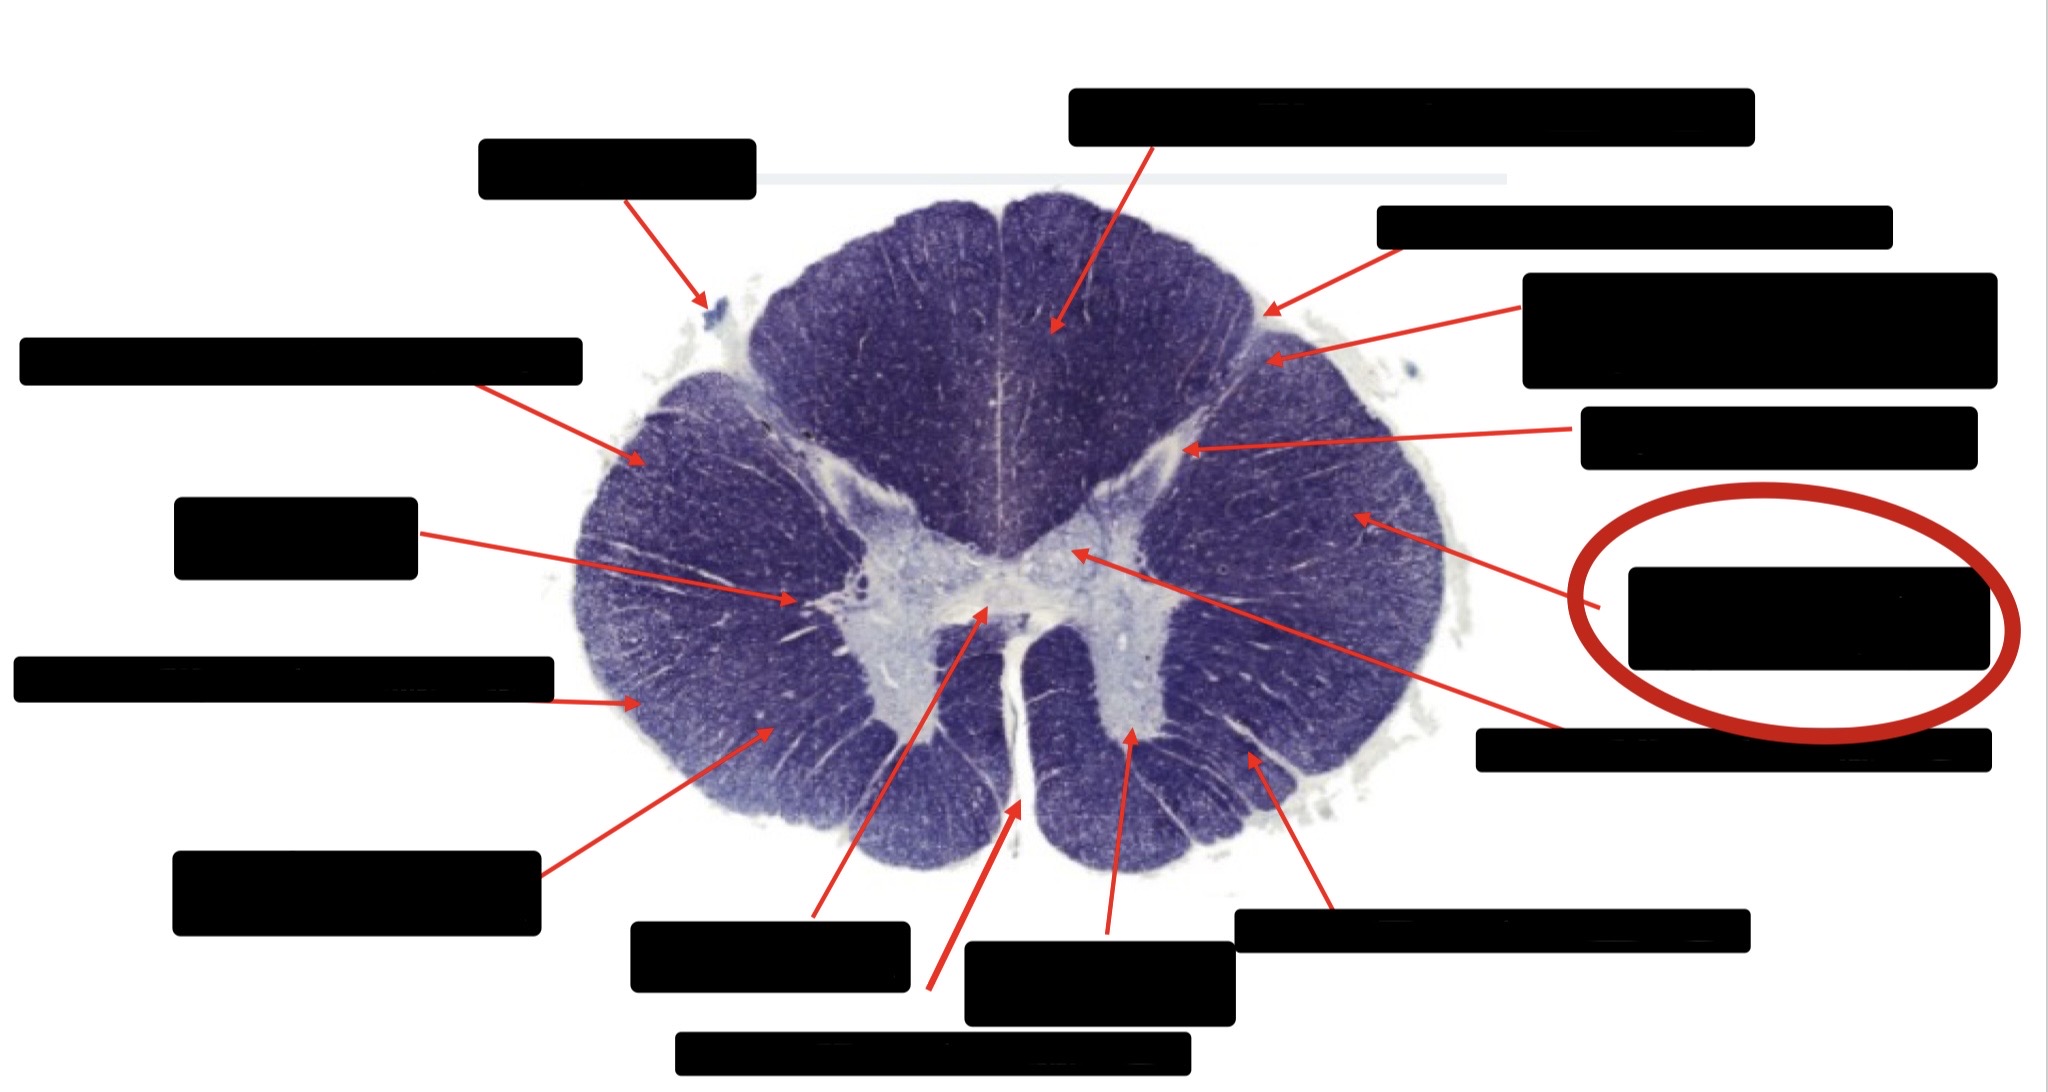

Posterior Column

Large Fiber Entry Zone

Posterior Spinocerebellar Tract

Clarke’s Nucleus

Anterior Spinocerebellar Tract

Ventral Root Fibers

Central Canal

Lissauer’s Tract & Small Fiber Entry Zone

Substantia Gelatinosa

Lateral Corticospinal Tract

Spinothalamic Tract

Anterior Horn Motor Neurons (Distal Muscles)

Anterior Horn Motor Neurons (Proximal Muscles)

Dorsal Rootlet

Lateral Horn

Spinothalmic Tract